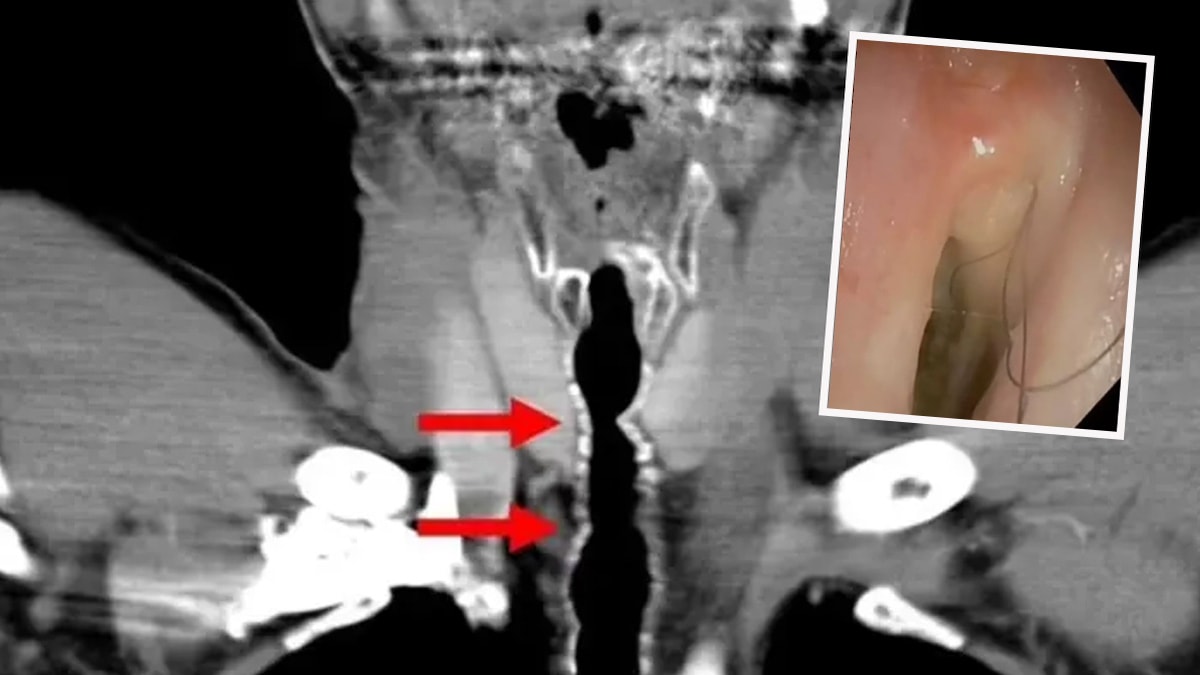

Hastanın şikayeti üzerine yapılan testler sonucunda ortaya çıkan sonuç şaşkına çevirdi. Boğazına gönderilen küçük bir kamera yardımıyla tespit edilen kıllar şaşkınlık yaratırken temizlenmesi de gerçekleştirildi.

Talihsiz hastaya endotrakeal kıllanma veya boğazda kıllanma adı verilen son derece nadir bir durum teşhisi konuldu. Kesin olarak aktarılmasa da doktorlar saç büyümesinin muhtemelen sigara içme alışkanlığından kaynaklandığına inanıyorlar.

American Journal of Case Report'ta yer alan yazılarada, bu tuhaf olayın türünün yalnızca ikinci vakası olduğu aktarıldı. Yine Avusturyalı bilim insanları, sigaranın boğaz iltihabını tetikleyebileceğini ve bunun da hücrelerin kıl köklerine dönüşmesine neden olabileceğini açıkladı.

Hasta 2020 yılında sigarayı tamamen bıraktı. Sonrasında ise saç kökünün yakılmasını içeren endoskopik argon plazma pıhtılaşması gerçekleştirdiler. İşlemden bir yıl sonra iki adet saç çıktı ve yeniden bir tedavi uygulandı. O zamandan beri hiçbir tüy geri dönmedi.